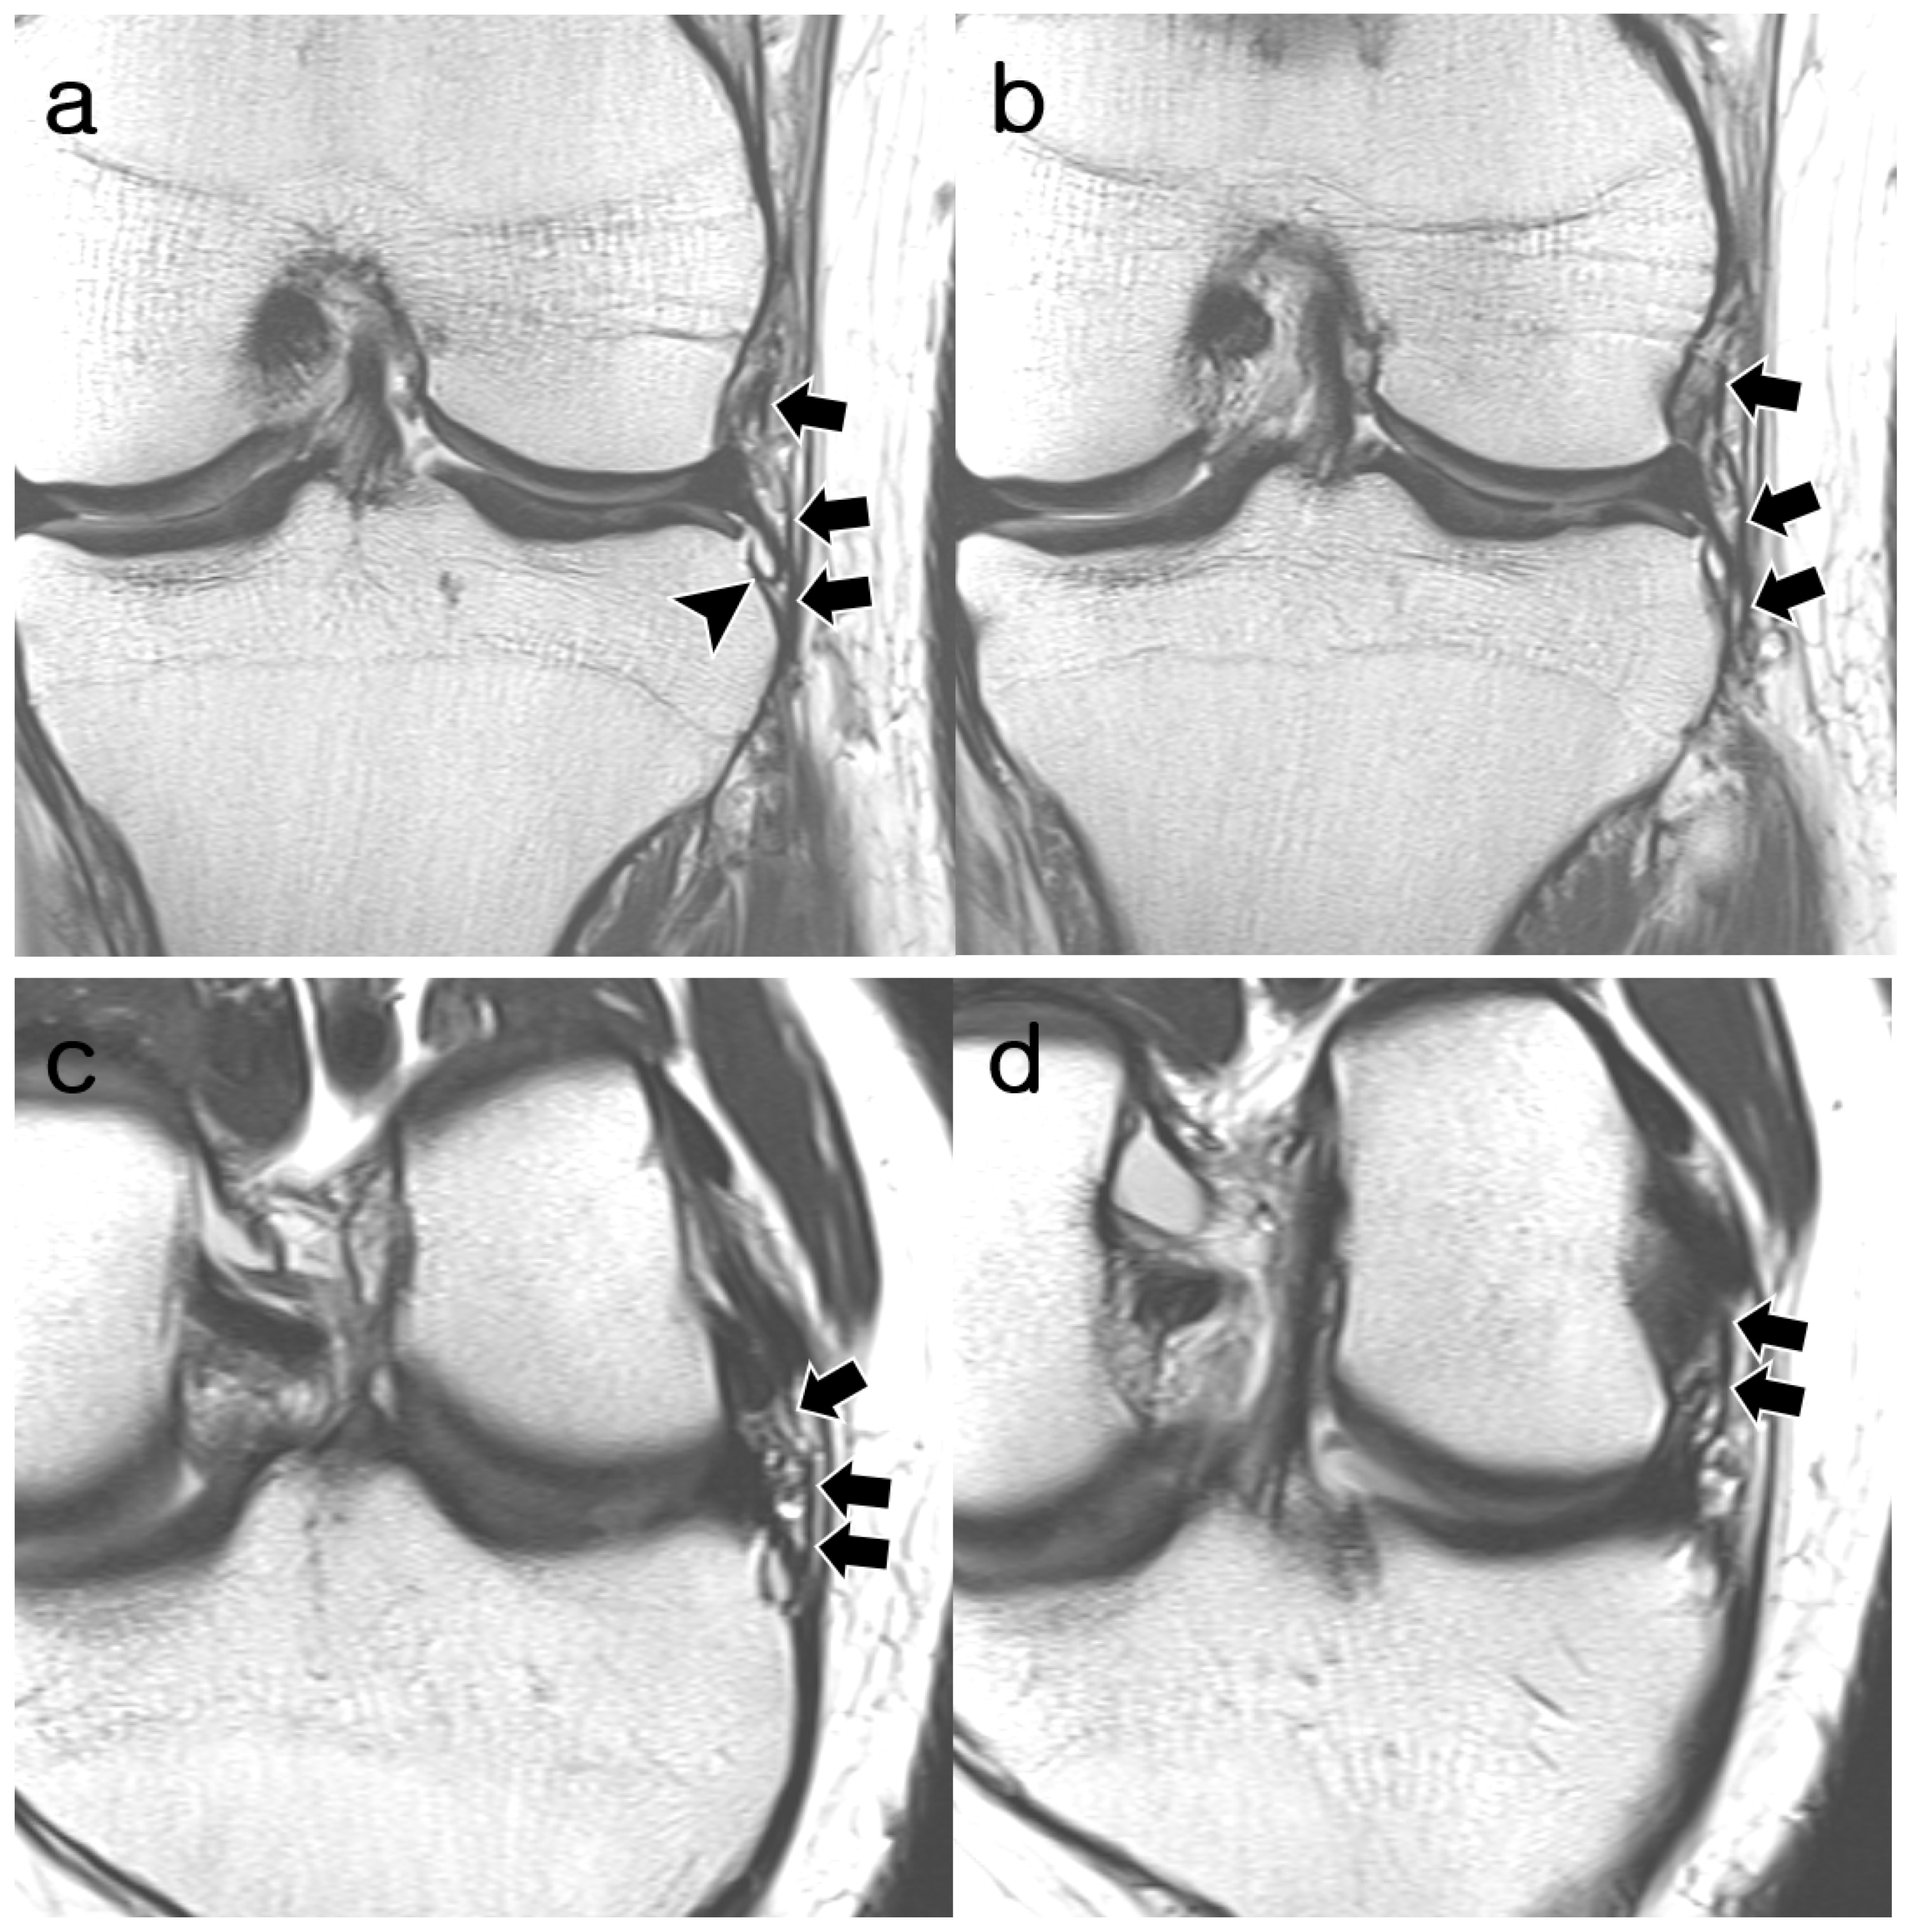

3.2. ALL Visibility

3.3. ALL Morphology